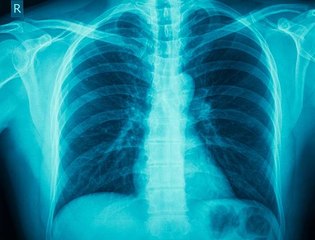

This Day in History: , German Scientist Discovers X-Rays .br November 8, 1895.br Wilhelm Conrad Rontgen's , discovery of X-rays happened accidentally as he conducted a test on cathode rays.br He noticed a glow on a screen br coated with chemicals. br Rontgen called the rays br that caused the glow X-rays.br After conducting more experiments, Rontgen discovered that X-rays could pass through human flesh, but not harder substances such as bone.br He also learned that they could br be photographed. The discovery br was hailed as a medical miracle.br X-rays were first used on a br battlefield during the Balkan War in 1897.